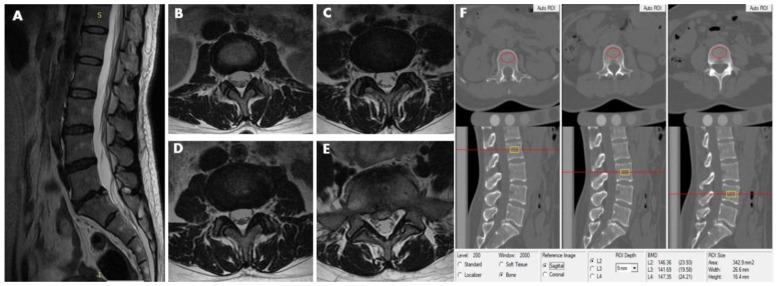

Little is known about the effect of lumbar intervertebral disc herniation (LDH) on lumbar bone mineral density (BMD), and few previous studies have used quantitative computed tomography (QCT) to assess whether the staging of LDH correlates with lumbar vertebral trabecular volumetric bone mineral density (Trab.vBMD). To explore the relationship between lumbar Trab.vBMD and LDH, seven hundred and fifty-four healthy participants aged 20-60 years were enrolled in the study from an ongoing study on the degeneration of the spine and knee between June 2014 and 2017. QCT was used to measure L2-4 Trab.vBMD and lumbar spine magnetic resonance images (MRI) were performed to assess the incidence of disc herniation. After 9 exclusions, a total of 322 men and 423 women remained. The men and women were divided into younger (age 20-39 years) and older (age 40-60 years) groups and further into those without LDH, with a single LDH segment, and with ≥2 segments. Covariance analysis was used to adjust for the effects of age, BMI, waistline, and hipline on the relationship between Trab.vBMD and LDH. Forty-one younger men (25.0%) and 59 older men (37.3%) had at least one LDH segment. Amongst the women, the numbers were 46 (22.5%) and 80 (36.4%), respectively. Although there were differences in the characteristics data between men and women, the difference in Trab.vBMD between those without LDH and those with single and ≥2 segments was not statistically significant ( > 0.05). These results remained not statistically significant after further adjusting for covariates ( > 0.05). No associations between lumbar disc herniation and vertebral trabecular volumetric bone mineral density were observed in either men or women.